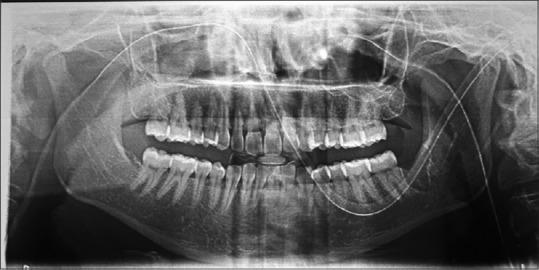

PAIN in the craniofacial and neck region can be both intriguing and equally frustrating for the surgeon. This is principally because there is a multitude of related pain syndromes in this region, many of which are lacking in physical signs. Diagnosis then becomes even more dependent on an accurate description of the pain in terms of character, localization, duration, radiation, relieving and exacerbating factors. Familiarity and identification of a more obscure causative factor in a particular case lends itself not only to liberate the patient but also an increased awareness of the practitioner for the need to consider the coinciding minute diagnostic points of otolaryngology, ophthalmology and rhinology besides dentistry and oral surgery. The characteristic elongation of a styloid process may explain some occasions of pharyngeal, ear pain and sometimes headache, which have defied exhaustive diagnostic studies. A large spectrum of signs and symptoms has been mentioned in various reports of Eagle's syndrome. Diagnosis can be made with careful clinical evaluation and confirmed with radiographs showing an elongated styloid process or calcification of the stylohyoid complex. Styloidectomy is the procedural choice for Eagle's syndrome having high success rate. In our case, the intraoral approach for styloidectomy was not the routine one, for which the post-operative outcome was exceptionally good without any complications.

颅面部和颈部区域的疼痛对于外科医生来说既引人关注又同样令人沮丧。这主要是因为该区域存在多种相关的疼痛综合征,其中许多缺乏体征。因此,诊断更加依赖于对疼痛的特征、定位、持续时间、放射部位、缓解和加重因素的准确描述。在特定病例中熟悉并识别出更隐匿的致病因素,不仅有助于使患者解脱病痛,还能提高从业者的认识,使其意识到除了牙科和口腔外科外,还需要考虑耳鼻喉科、眼科和鼻科的细微诊断要点。茎突的特征性延长可能解释了一些尽管经过详尽诊断研究仍无法明确病因的咽部、耳部疼痛,有时还有头痛的情况。在关于鹰综合征的各种报告中提到了广泛的体征和症状。通过仔细的临床评估可以做出诊断,并通过X线片显示茎突延长或茎突舌骨复合体钙化来确诊。茎突切除术是治疗鹰综合征的手术选择,成功率较高。在我们的病例中,茎突切除术采用的口内入路并非常规方法,术后效果非常好,没有任何并发症。